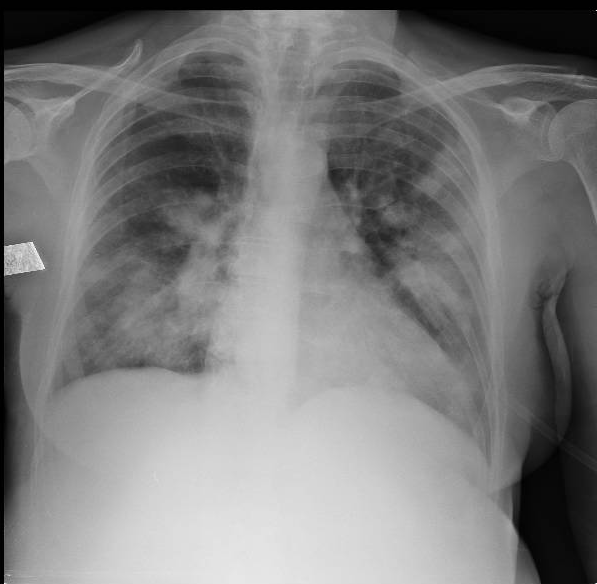

Radiografia de Tórax

TC de tórax sin contraste

Hemocultivos negativos. Urocultivo negativo. Lavado bronquialveolar sin rescates pero compatible con hemorragia alveolar.

Se interpretó una granulomatosis esosinofílica con poliangeítis (GEPA) con compromiso grave a nivel neurológico periférico y síndrome «pulmón-riñón» por compromiso pulmonar (hemorragia alveolar) y renal (proteinuria). Se indicó tratamiento inmunosupresor con dosis altas de esteroides e inducción de remisión con ciclofosfamida 1 g.